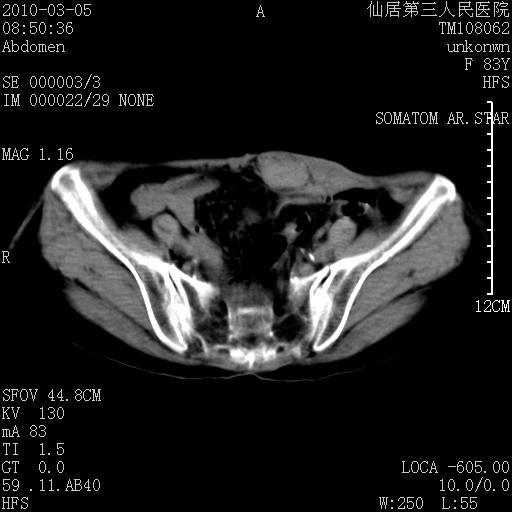

标题: CT24879:腹直肌病变。在线等。 [打印本页]

标题: CT24879:腹直肌病变。在线等。

女性,83y,腹痛一周。

考虑:左侧腹直肌神经纤维瘤可能

神经纤维瘤—伴有出血?

有无外伤,血肿或韧带样瘤

考虑左侧腹直肌血肿,肿瘤性病变待排。

增强看看,mfh可能性大,次之可考虑血肿、bfh、转移瘤、神经纤维瘤、侵袭性韧带样纤维瘤等。肝内钙化灶,右肾结石。

支持血肿

支持腹壁纤维肉瘤

血肿,纤维瘤,子宫内膜异位都有可能。